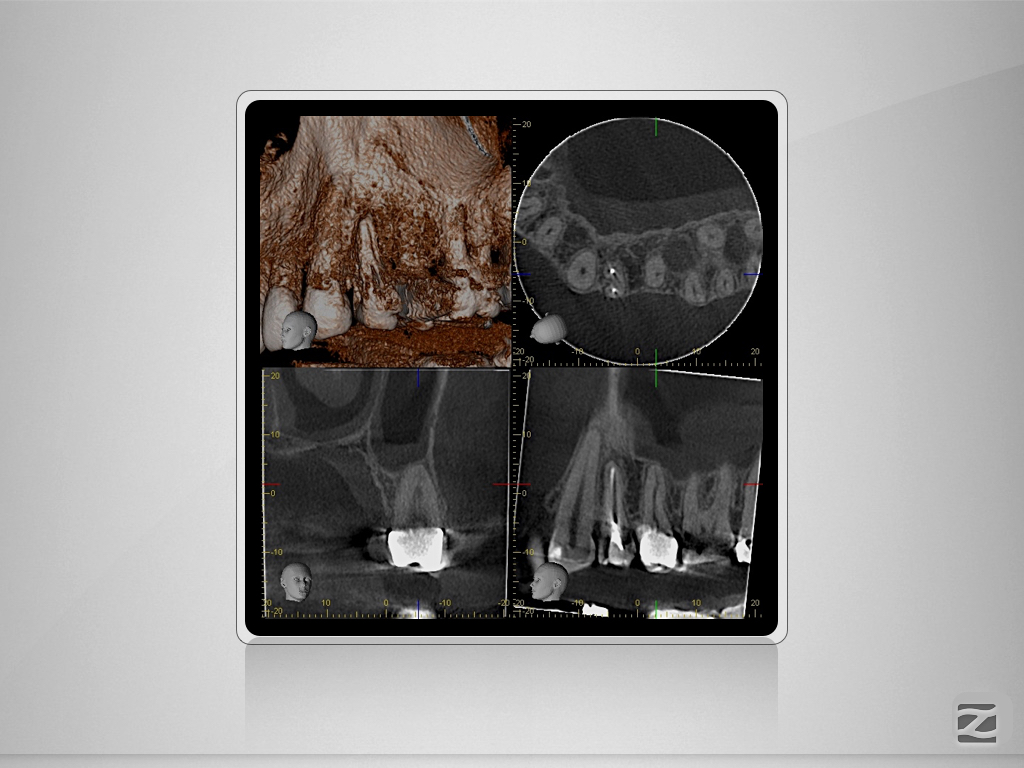

15D.002

Therapieplanung in 3D